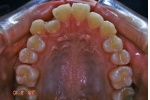

| 治療前後の比較